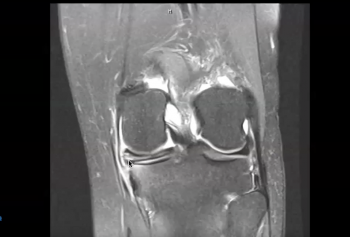

How to Read Knee MRI of Medial Meniscus Tear | Horizontal Cleavage Tear | Colorado Knee Surgeon

How to Read Knee MRI of Meniscal Root Tear | Knee Surgeon Colorado

How to Read a Knee MRI for Meniscus Tears